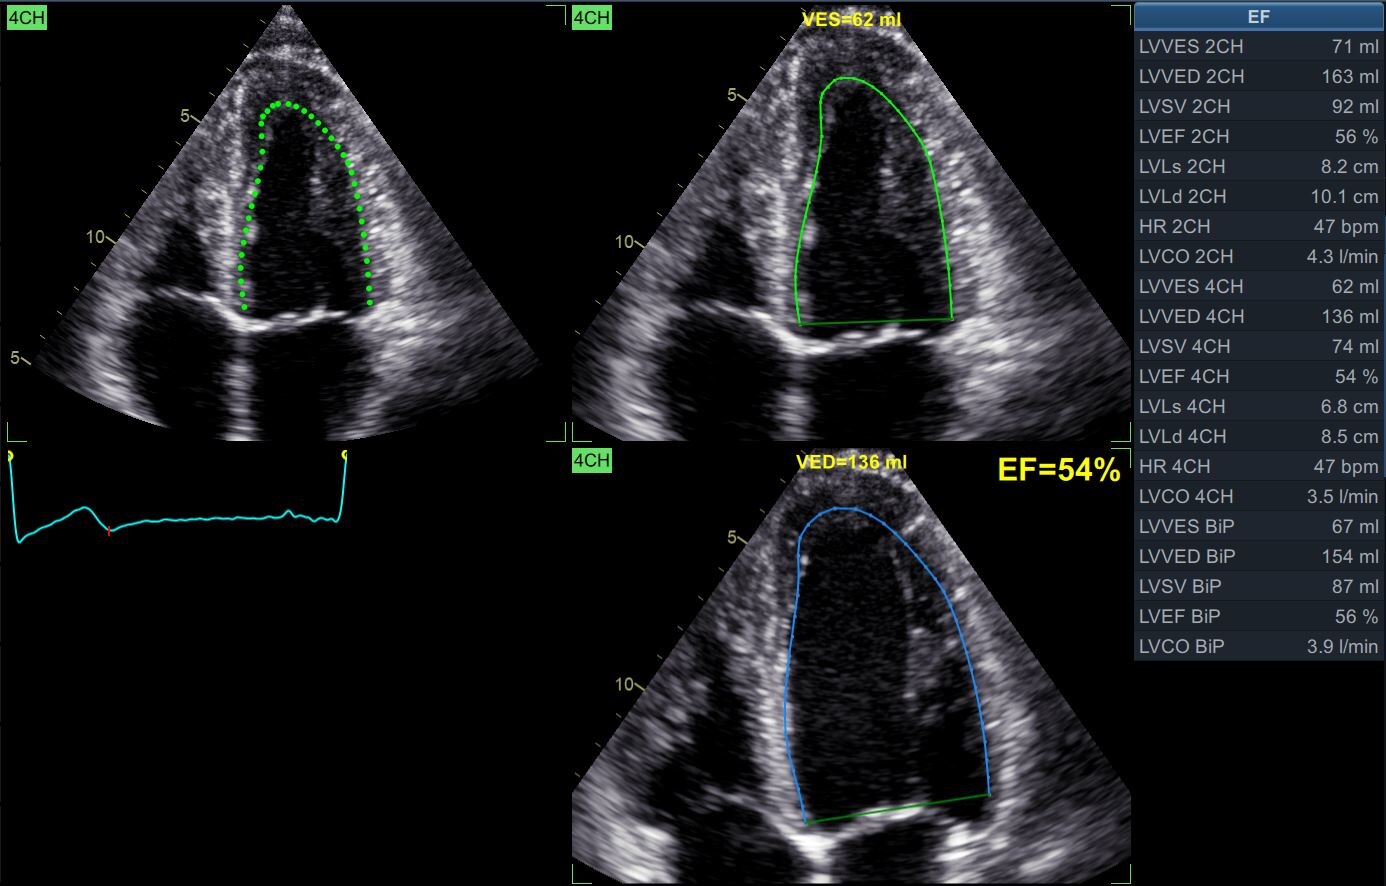

Auto EF 2.0**

Define the care path Quantification with Vivid E95 is all about helping providers evaluate problems and pursue the path forward. Count on a full suite of intuitive tools to make your work easy and efficient. Quickly, accurately and thoroughly quantify left and right ventricular wall motion and other key functions.